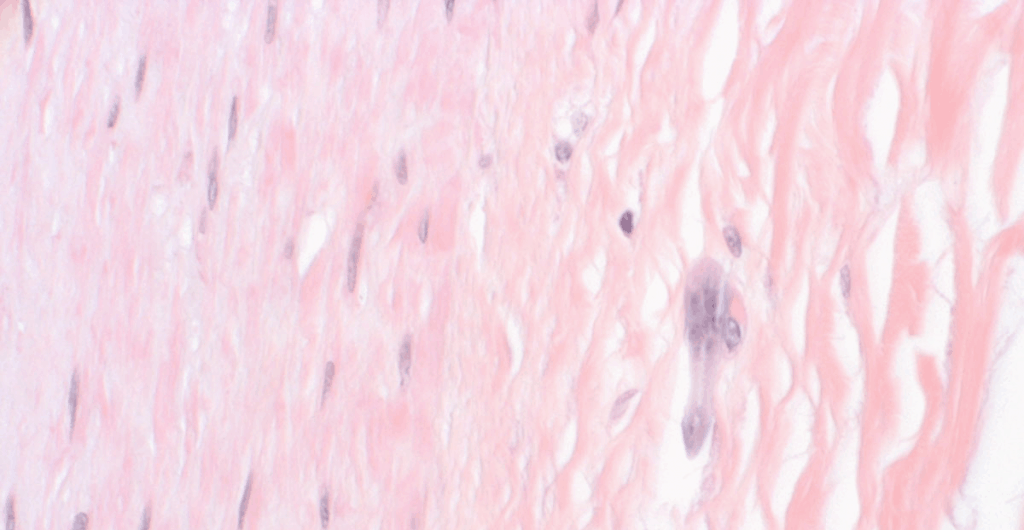

LYME DISEASE TREATMENT IN PREGNANCY CONT

QUESTION: I have a 33yoF who I have seen twice for Lyme disease. She had a…